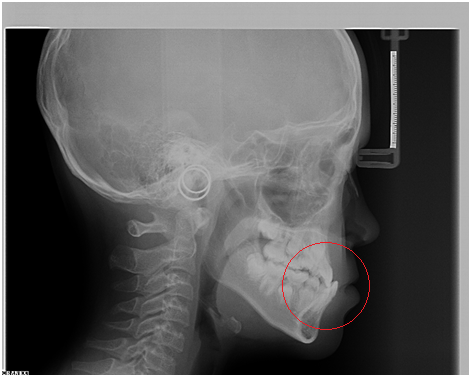

【口腔侧位片】

◆地包天